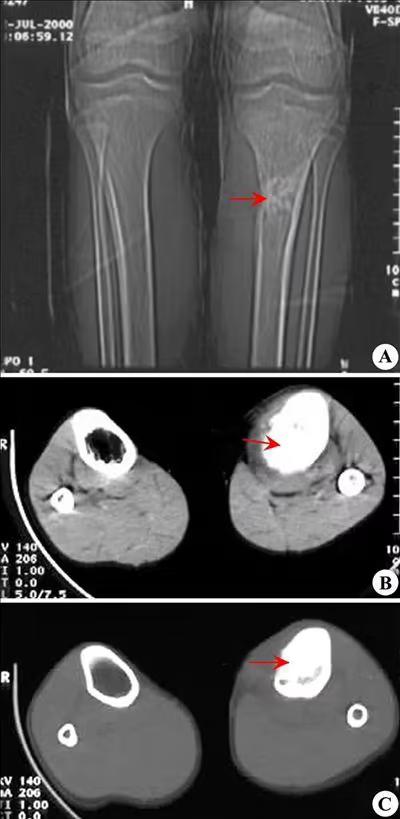

X光线提示,小白的右臂骨质破坏十分严重,在肱骨上有一片黑影,骨科医生建议小白补充CT检查,经过多位骨科专家的鉴定,确定这就是罕见的骨肉瘤,骨科医生对小白的爸妈解释了这种严重的骨骼癌症,然后建议他们马上到市中心的肿瘤医院做检查,小白的爸妈只是普通的村民,那里听说过这么严重的疾病,听完医生讲解后,小白的妈妈直接就哭晕了过去。